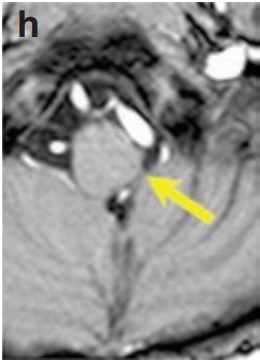

更让我们欣慰的是漫长的随访结果。术后三年,复查的增强MRI(图h)显示,肿瘤无任何复发迹象。

而当年的小婴儿,已成长为一个精神抖擞、帅气阳光的小少年(图i),没有任何神经功能障碍,快乐地享受着他的童年。